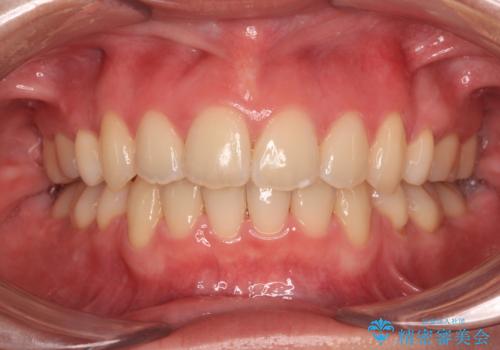

[ マウスピース矯正 ] 出っ歯に見える前歯を改善したい

![[ マウスピース矯正 ] 出っ歯に見える前歯を改善したいの症例 治療前](https://seimitsushinbi.jp/wp/wp-content/uploads/2023/10/IMG_6858-500x350.jpg?v=1697014973)

![[ マウスピース矯正 ] 出っ歯に見える前歯を改善したいの症例 治療後](https://seimitsushinbi.jp/wp/wp-content/uploads/2023/10/8a6c9bf89570c0c75da0a5fabd1cd70e-500x350.jpg?v=1697014858)